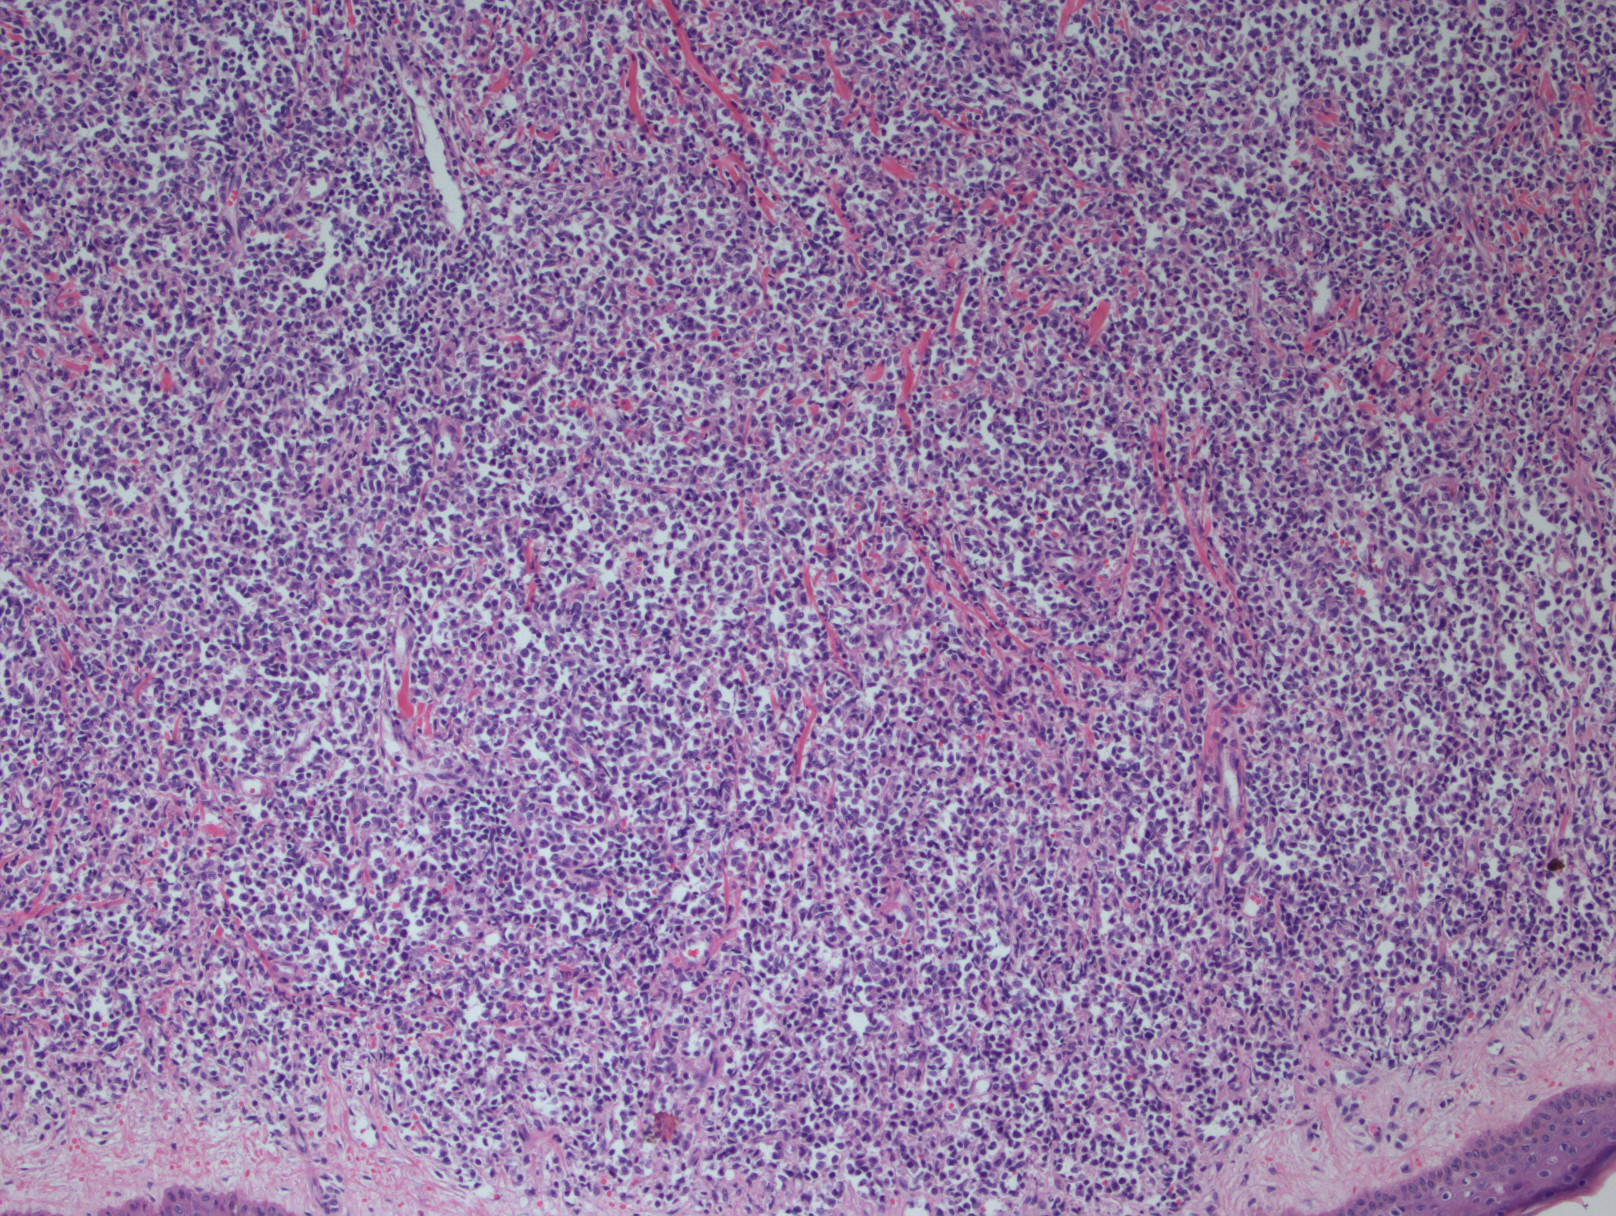

形态学:肿瘤细胞呈现弥漫生长,具母细胞特征(可类似淋巴母细胞或髓系母细胞):中等大小、形态单一、核轻度不规则、染色质细腻、一到多个核仁、胞质细少,无颗粒。在皮肤,通常浸润真皮,最终延及皮下,但不累及表皮;在骨髓,呈现稀少或成片间质浸润,涂片有时可见肿瘤细胞有膜下微小空泡及包膜伪足;在淋巴结,常侵犯髓区或滤泡间(白血病侵犯模式)。一般不出现凝固性坏死和血管中心性浸润。